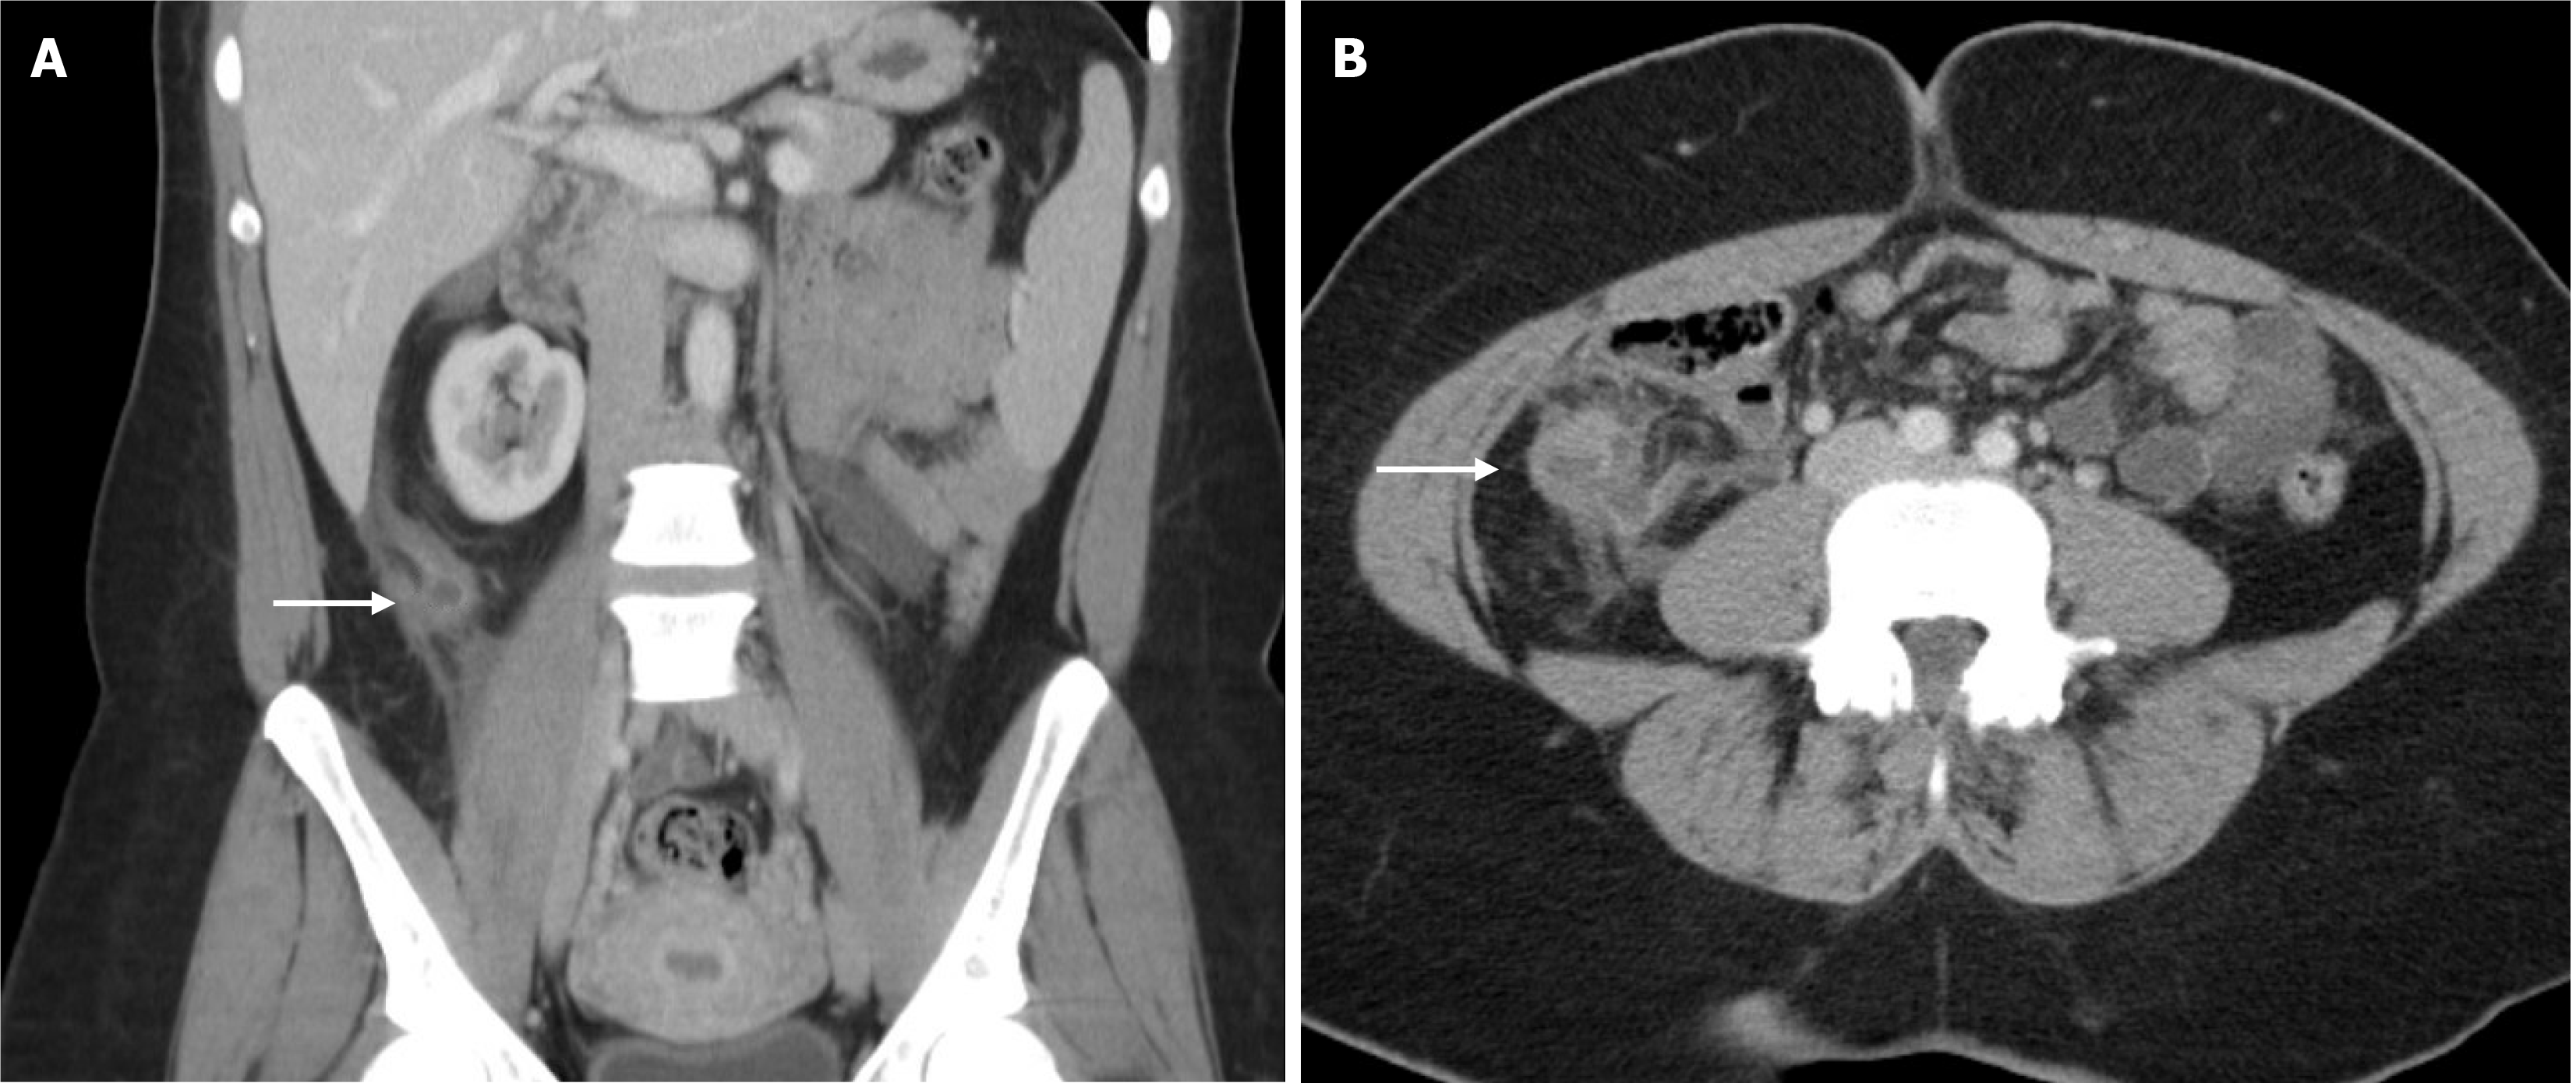

Abdominal computed tomography revealed a fluid-filled and distended appendix measuring 1.2 cm in diameter with adjacent fluid and fat stranding; no extraluminal gas was detected (Figure 1).